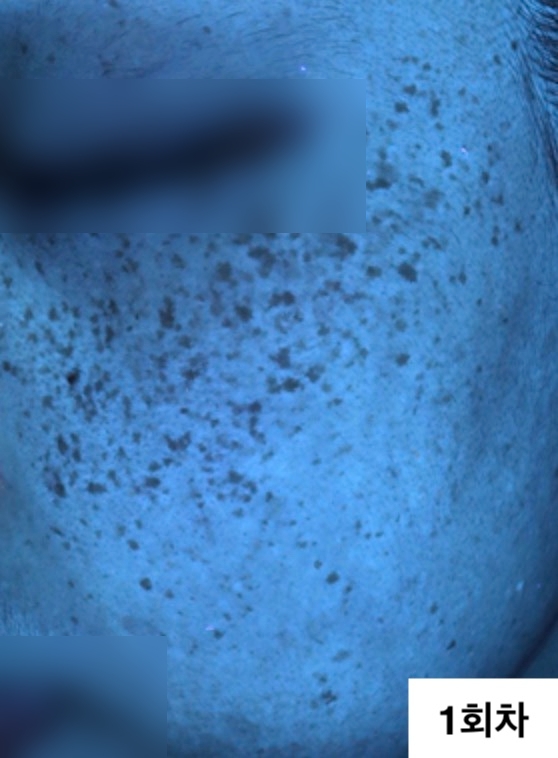

자외선광 1회차 / 10회차

2024.12.24

2025.04.04